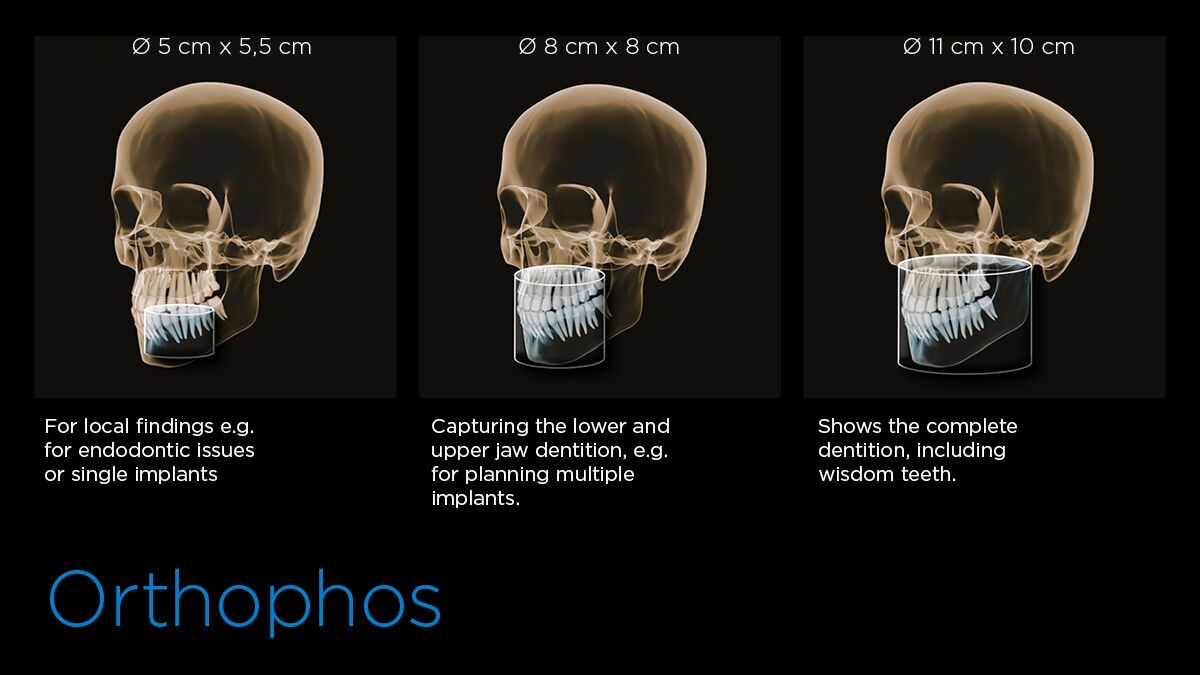

从ø 5cm x 5.5cm到ø 11cm x 10 m。

可根据您的需求调节立体图像大小,从Ø 5 x 5.5cm到Ø 11 x 10cm不等。

| 视野 | ø5×5.5 cm, ø8×8 cm, ø11×10(可选) |